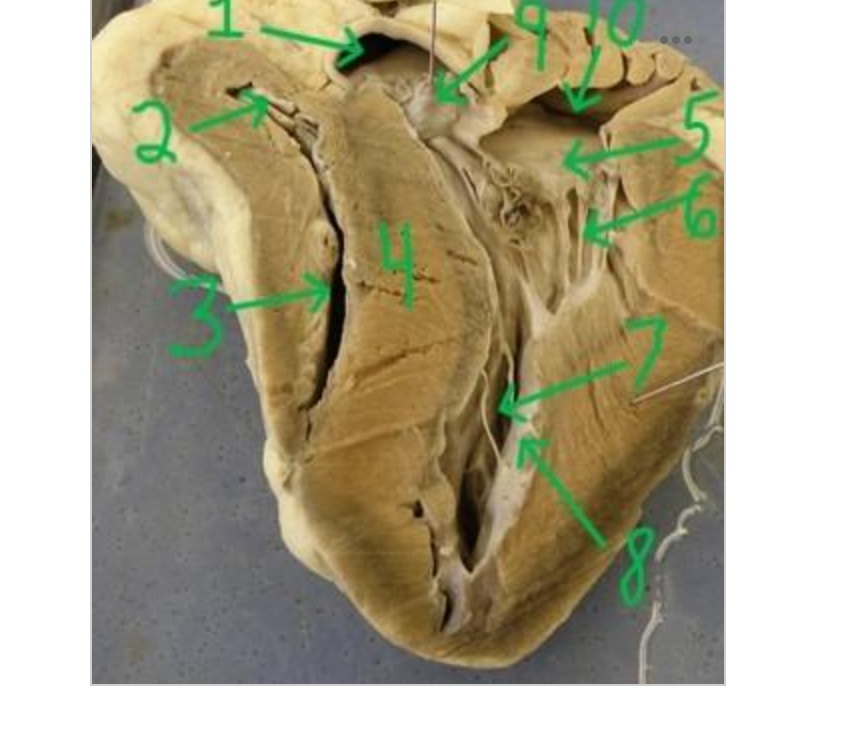

what is 1

right atrium

what is 2

tricuspid valve

what is 3

right ventricle

what is 4

interventricular septum

what is 5

left atrium

what is 6

mitral valve

what is 7

ductus arteriosus

what is 8

pulmonary semilunar valve